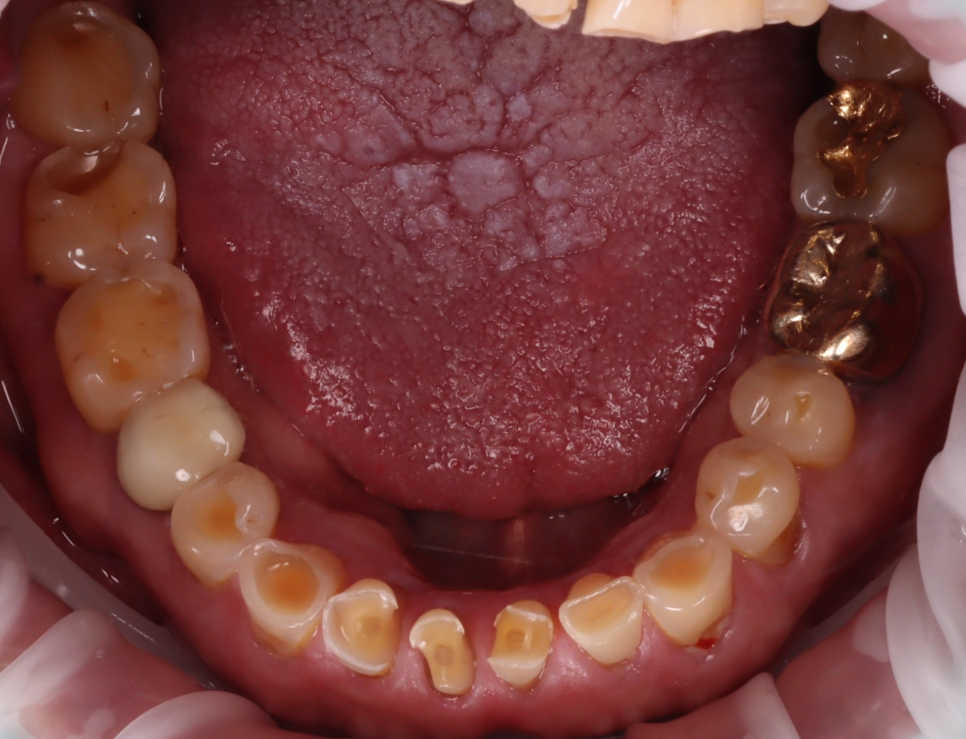

또, 아랫니가 많이 닳아있어 깊게 무는 형태인 'Deep bite(딥바이트)' 라고 부르는 과개교합 상태였죠.

오랜 시간 서로 부딪히며 위아래가 서로를 갈아버린 흔적이죠.

촬영일 : 251013

양쪽 작은 어금니 쪽에는 잇몸 가까이 패인 마모 부위도 있었고 찬물이나 칫솔질 때 "시큰시큰하다"라고 하셨어요.

환자분은 “아래 앞니가 많이 닳았어요"라고 말씀하셨지만 실제로는 아래 앞니에만 문제가 있는 것이 아니라 전체적인 교합, 마모 패턴을 같이 봐야 하는 상황이었어요.

아래는 크라운이 필요한 상황이었어요.